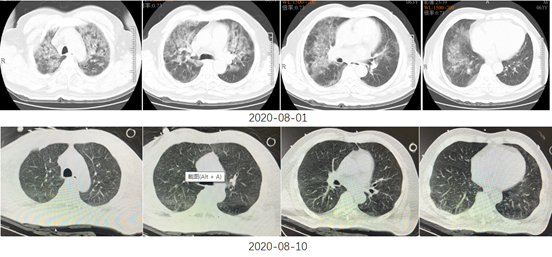

氧合指数进一步改善(289 mmHg)。

于2020年8月12日脱机拔管(插管9天),高流量吸氧装置续贯。

炎症标志物、心肌酶、BNP、黄疸、肝酶等指标逐步恢复正常。

8月14日停用青霉素。

康复锻炼+心理干预。

8月18日随访心超未见异常;心电图示窦性心律。

8月21日痊愈出院。